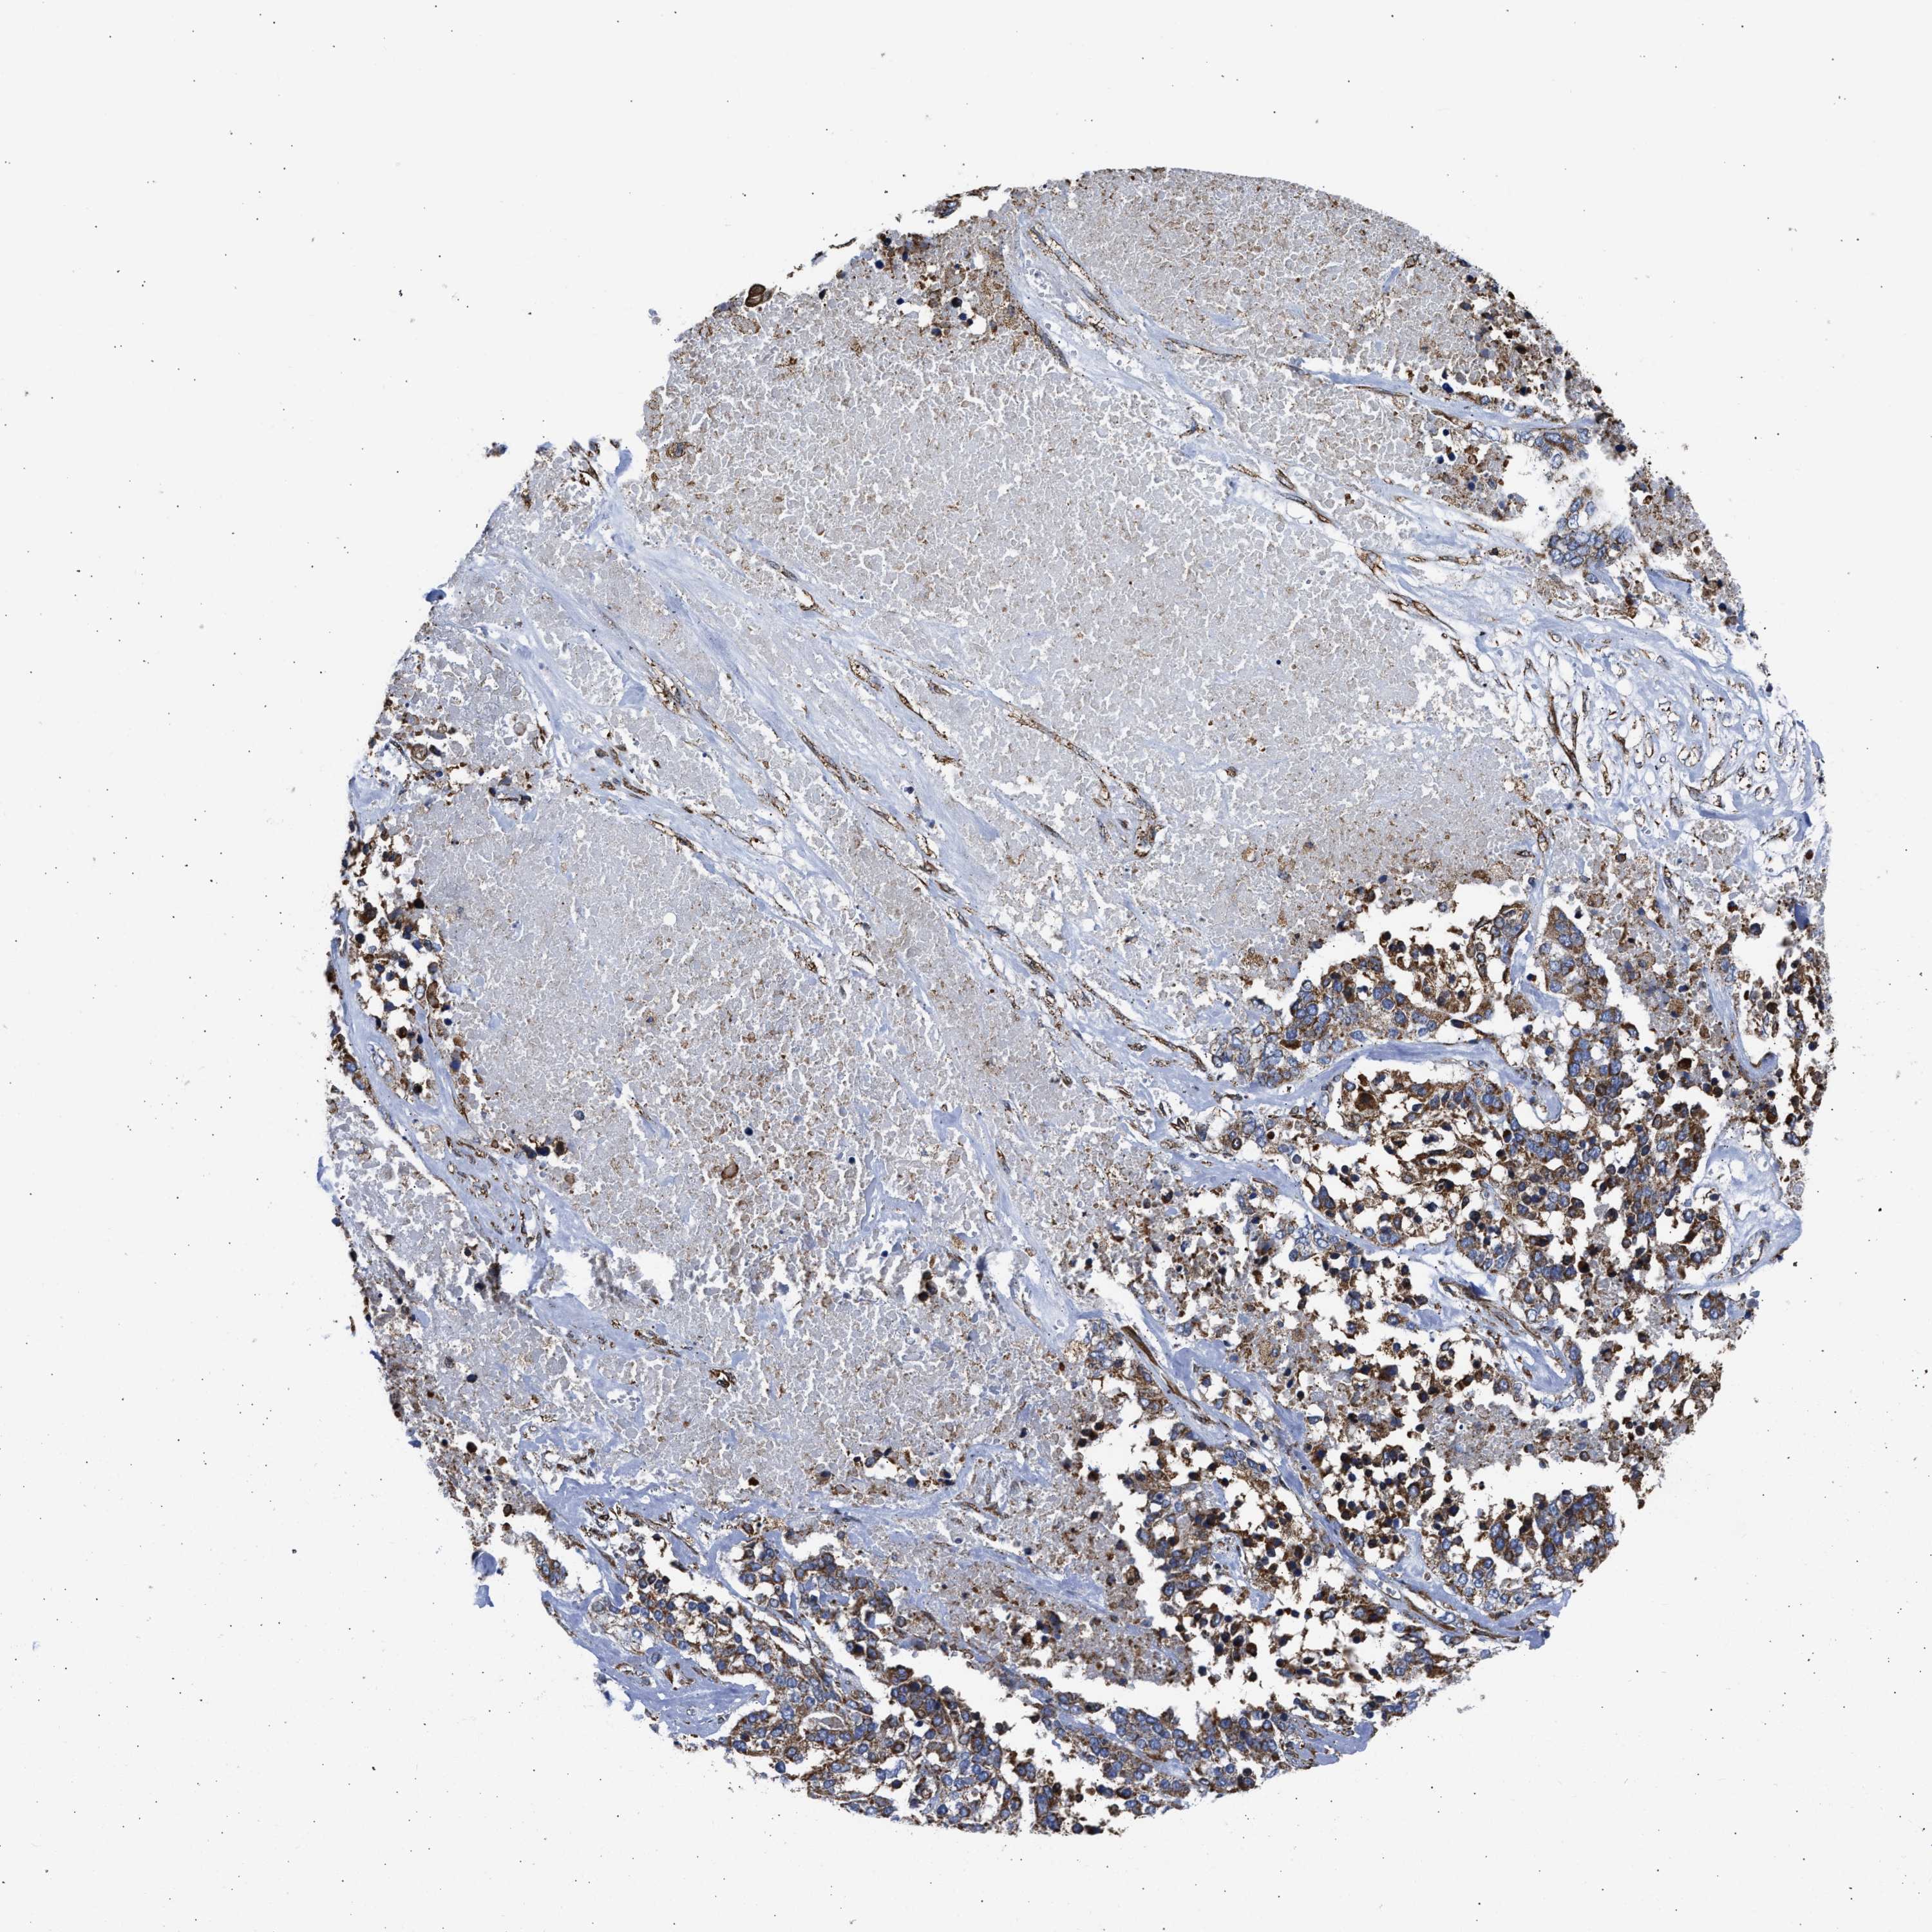

OVARIAN CANCER - Protein expressioni

A mouse-over function shows sample information and annotation data. Click on an image to view it in a full screen mode. Samples can be filtered based on level of antibody staining by selecting one or several of the following categories: high, medium, low and not detected. The assay and annotation is described here.

Note that samples used for immunohistochemistry by the Human Protein Atlas do not correspond to samples in the TCGA dataset.

Antibody stainingi

Antibody staining in the annotated cell types in the current human tissue is reported as not detected, low, medium, or high, based on conventional immunohistochemistry profiling in selected tissues. This score is based on the combination of the staining intensity and fraction of stained cells.

Each image is clickable and will lead to virtual microscopy that enables deeper exploration of all samples and also displays staining intensity scores, fraction scores and subcellular localization as well as patient and tissue information for each sample.

Antibody CAB004222

Cystadenocarcinoma, serous, NOS

Cystadenocarcinoma, mucinous, NOS

Carcinoma, endometroid

Carcinoma, NOS